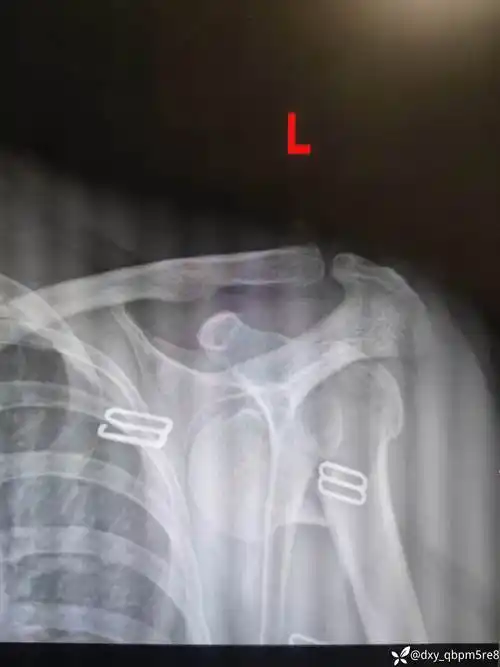

一例左肩关节脱位伴肱骨近端骨折病例